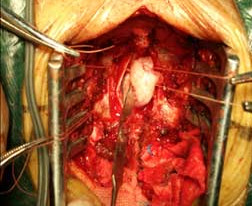

椎管內(nèi)腫瘤 椎管內(nèi)腫瘤術(shù)中